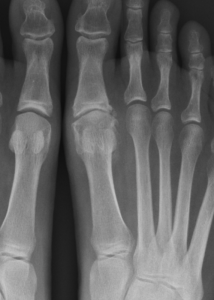

Figure1 and 2: Pre op x-rays showing joint degenerating including joint space narrowing, bone spurs and loose bone fragments.